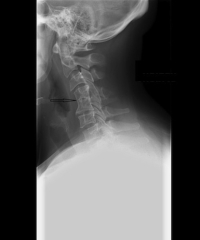

An Overview of Klippel Feil Syndrome

Klippel Feil Syndrome stems from the time of human development in the uterus. In embryological terms, humans start to form the spine through structures called somites. These somites develop soon after inception and start forming the vertebra by separating at about 3-8 weeks of development. Klippel Feil Syndrome is a failure of segmentation of one or more of these somites in the neck. In other words, the segments don’t separate. This causes, in effect a “fusion” of the two cervical vertebral segments.

Klippel Feil Syndrome is normally found as an incidental finding. This means that this congenital fusion normally causes no symptoms by itself. There might be preexisting decreased range of motion of the neck, but most people with this condition would not notice this decreased motion.

The main problem with Klippel Feil Syndrome is that normal degenerative changes occur around the fusion and eventually, symptoms occur from these degenerative changes. These are the typical complaints that most individuals have who do not have Klippel Feil Syndrome suffer from; neck pain, stiffness, shoulder and arm pain and nerve compression symptoms.